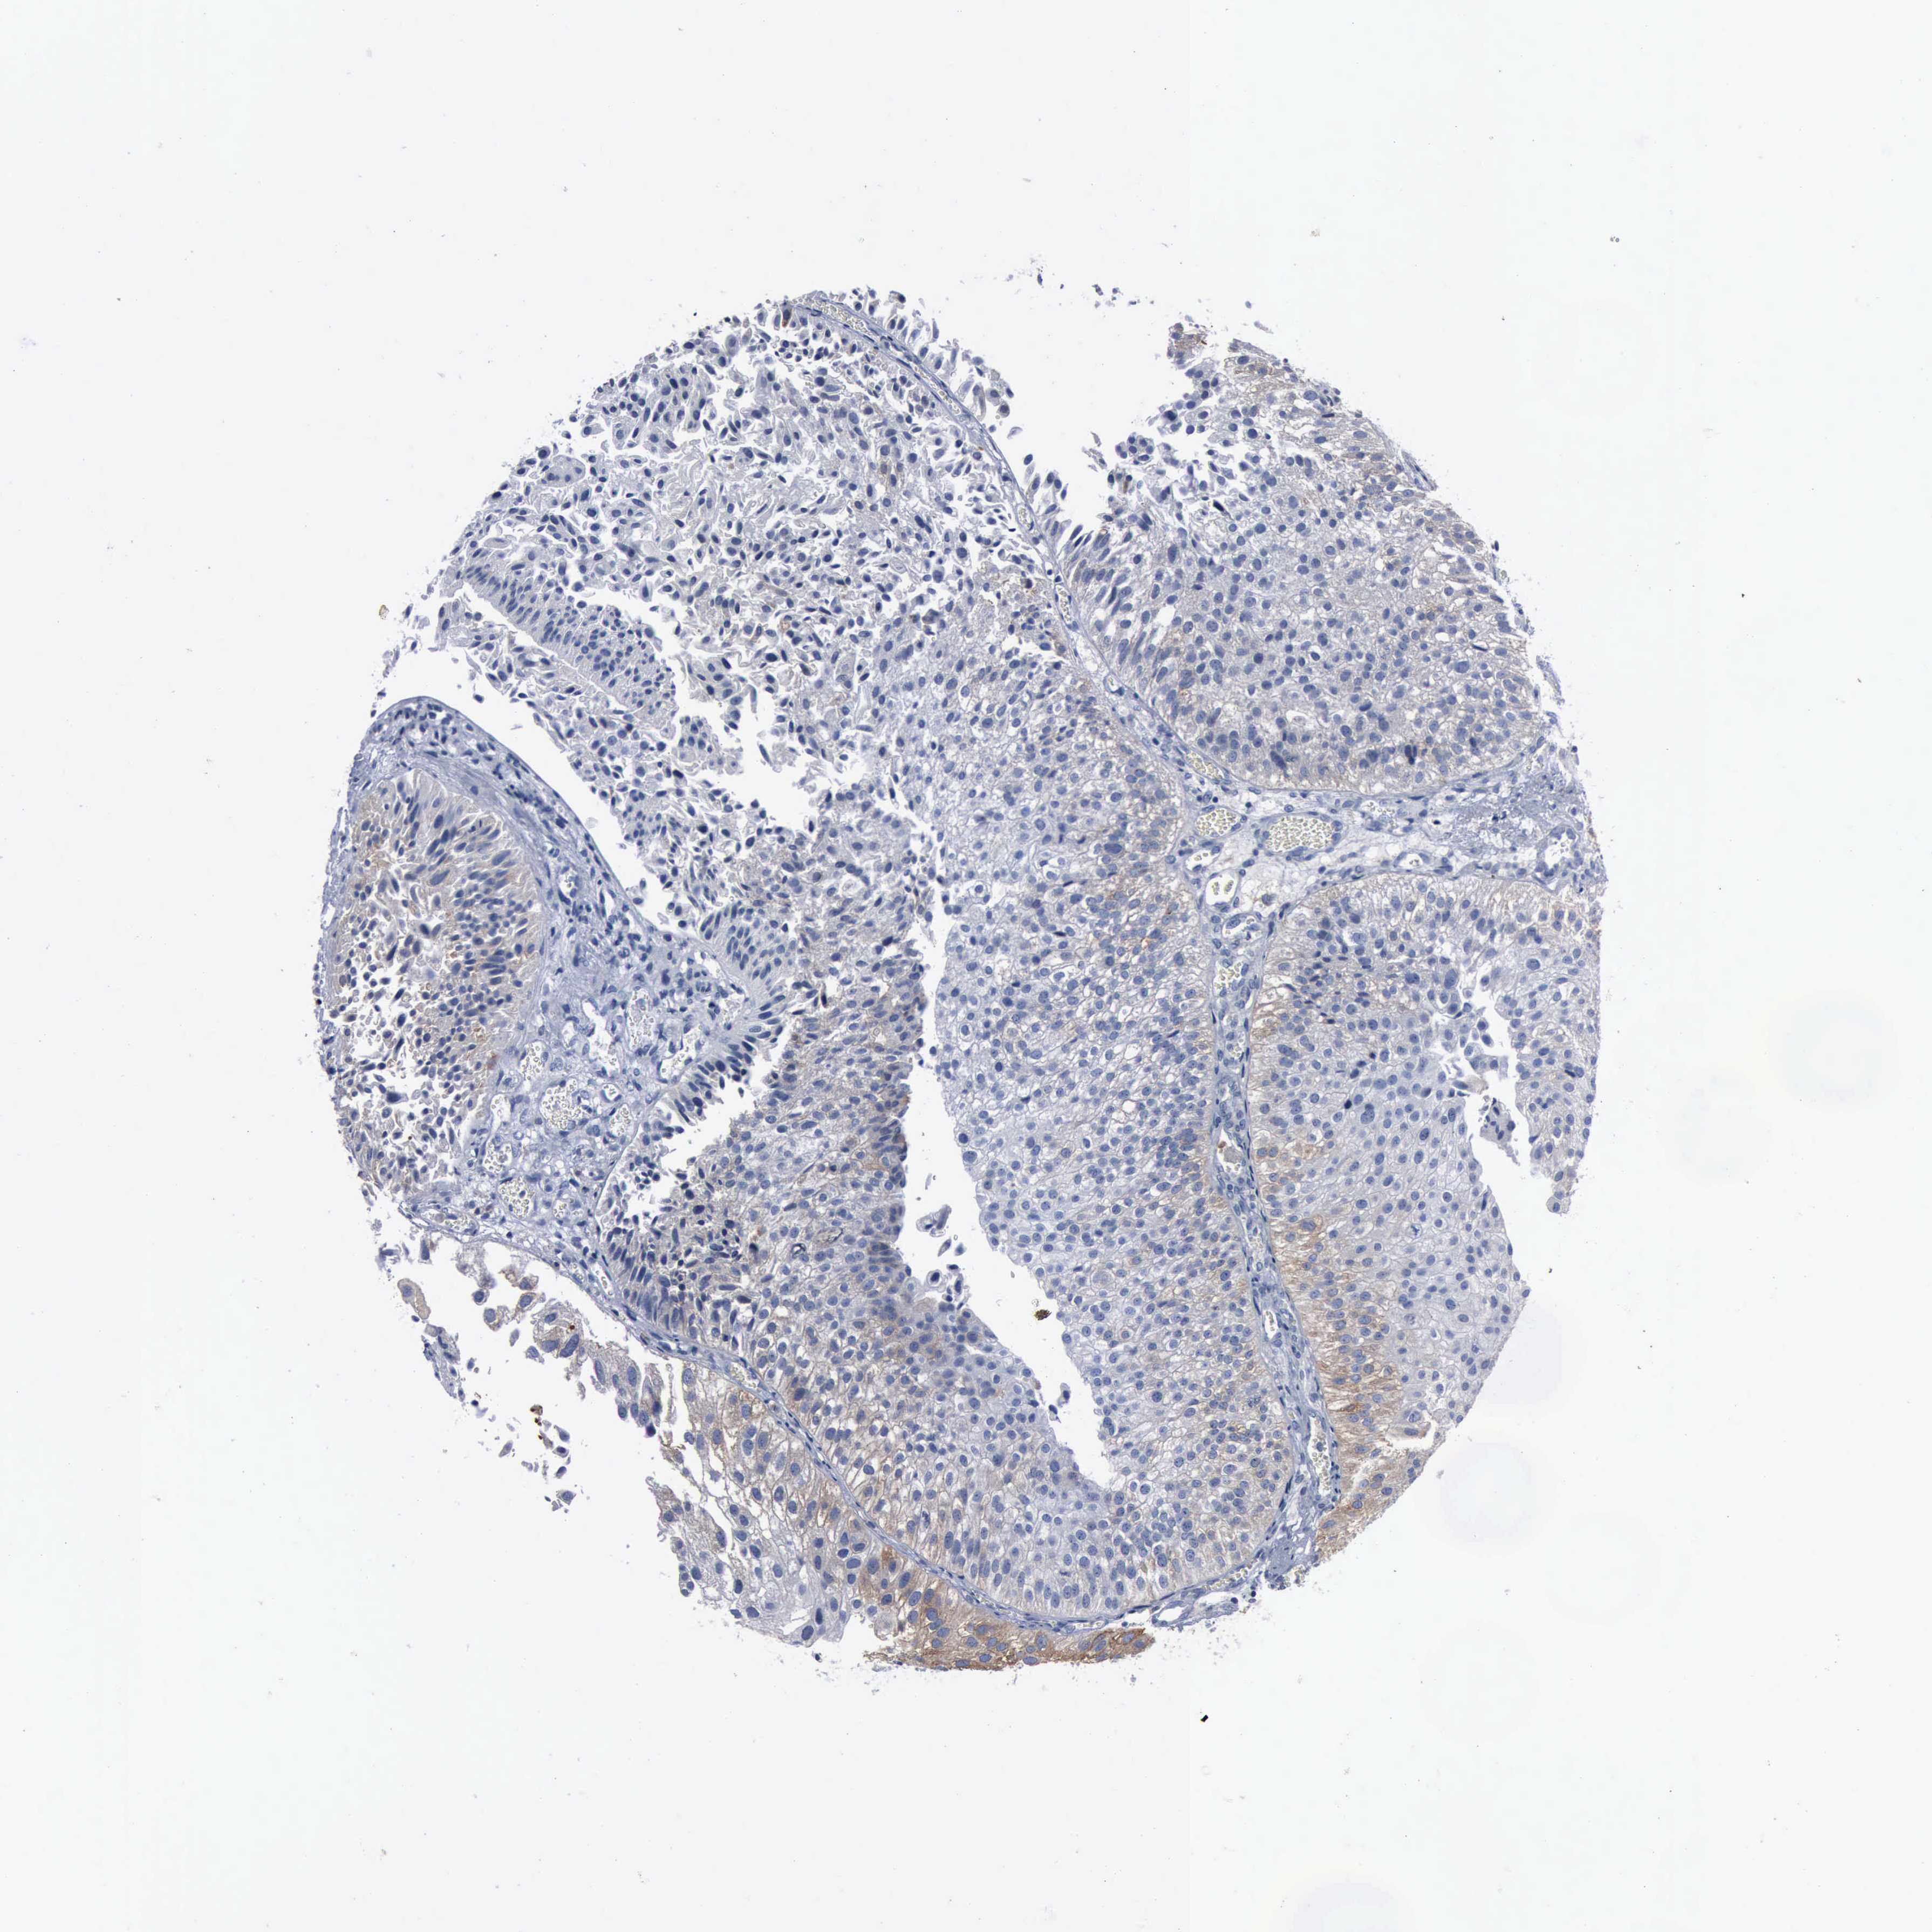

UROTHELIAL CANCER - Protein expressioni

A mouse-over function shows sample information and annotation data. Click on an image to view it in a full screen mode. Samples can be filtered based on level of antibody staining by selecting one or several of the following categories: high, medium, low and not detected. The assay and annotation is described here.

Antibody stainingi

Antibody staining in the annotated cell types in the current human tissue is reported as not detected, low, medium, or high, based on conventional immunohistochemistry profiling in selected tissues. This score is based on the combination of the staining intensity and fraction of stained cells.

Each image is clickable and will lead to virtual microscopy that enables deeper exploration of all samples and also displays staining intensity scores, fraction scores and subcellular localization as well as patient and tissue information for each sample.

Antibody HPA000962

Antibody HPA004119

Staining

High

Medium

Low

Not detected

Intensity

Strong

Moderate

Weak

Negative

Quantity

>75%

75%-25%

<25%

None

Location

Nuclear

Cytoplasmic/membranous

Cytoplasmic/membranous,nuclear

Urothelial carcinoma, High grade